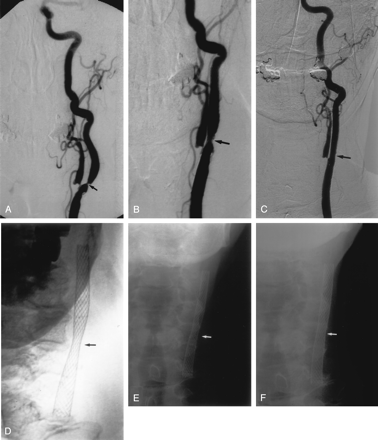

Immediate poststent angiography showed a moderate improvement in the degree of stenosis in most patients. In some patients, the improvement was dramatic, with one stenosis decreasing from 99% to 29% (Fig 1). In most patients, however, the improvement was more gradual (Fig 2). On average, the angiographic stenosis improved from 83% to 49% immediately after stent placement (median, 48%; range, 29–73%). Two patients still had stenosis in the severe range (>70%); the worst of these was 73%. Both improved by 2–3 months to 18% and 20% residual stenosis, respectively. At last follow-up in all patients the mean residual stent stenosis was 19% (median, 16%; range, 0–54%). Comparing matched pairs of measurements in the same patients over several time intervals, the maximum stent expansion occurred during the procedure, followed by a gradual further expansion over the next 4–12 months (Fig 3). After the first year, the appearance remained stable out to 44 months.

A, Right CCA digital subtraction arteriogram (DSA), lateral view, showing a very severe atherosclerotic stenosis of the proximal ICA, >95% by NASCET criteria (arrow).

B, Repeat DSA, lateral view, immediately poststenting alone, without balloon angioplasty, showing a reduction in the degree of stenosis to approximately 29%.

A, Left CCA DSA, AP view, showing a severe stenosis of the proximal ICA, measuring approximately 76% (arrow).

B, Repeat DSA, AP view, immediately poststenting without balloon angioplasty, showing reduction of the stenosis to approximately 50% (arrow).

C, Follow-up DSA, AP view, 3 years poststenting alone, shows no residual ICA stenosis.

D, E, and F, Conventional AP radiographs of the neck immediately poststenting (D), 1 month (E) and 8 months (F) poststenting, showing progressive opening of the stent waist (arrow), with maximum expansion occurring in the 1st month postprocedure.